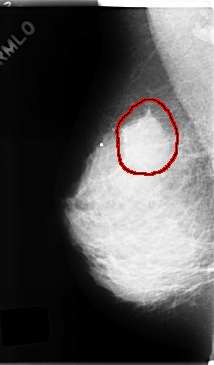

FILE: C_0166_1.RIGHT_MLO.OVERLAY

TOTAL_ABNORMALITIES 1

ABNORMALITY 1

LESION_TYPE MASS SHAPE ROUND MARGINS SPICULATED

ASSESSMENT 5

SUBTLETY 5

PATHOLOGY MALIGNANT

TOTAL_OUTLINES 1

BOUNDARY